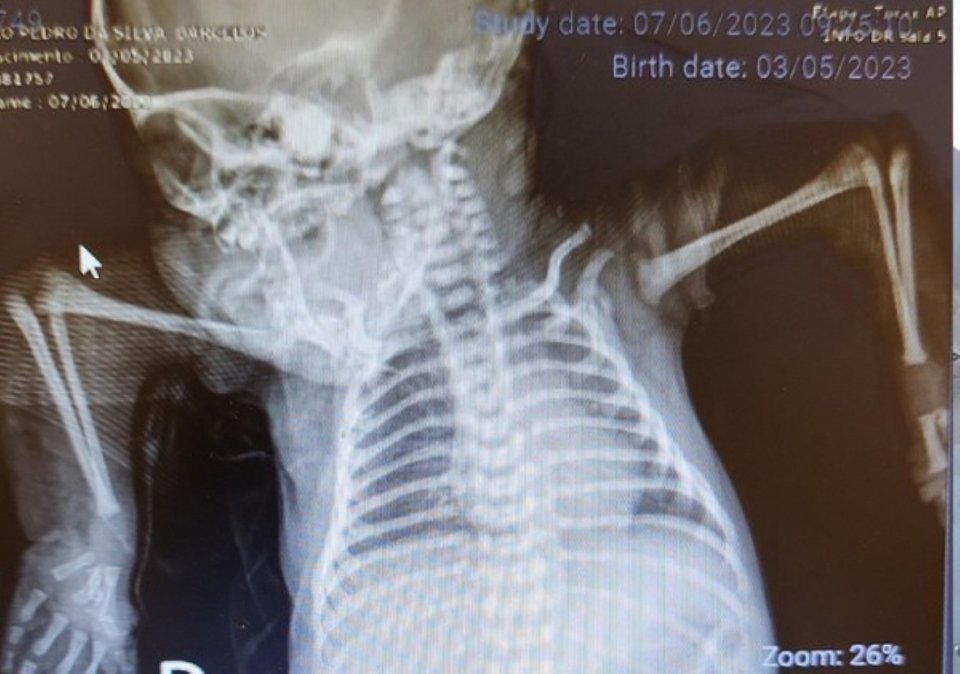

Αποτέλεσμα της πάθησης αυτής ήταν το μωρό να γεννηθεί με τους ώμους του στραμμένους προς τα κάτω και τους αγκώνες του προς τα πάνω. Οι αρθρώσεις του ήταν σκληρές και κοντές, με αποτέλεσμα να μην μπορεί να κινήσει τα χέρια ή τα δάχτυλά του.

Η Maria da Conceição Soares, εργοθεραπεύτρια που ήταν υπεύθυνη για την περίπτωση του João Pedro, σοκαρίστηκε όταν τον είδε. «Είχε περάσει από όλο το νοσοκομείο και κανείς δεν είχε δει ποτέ κάτι τέτοιο. Η θέση στην οποία γεννήθηκε είναι πολύ σπάνια», εξηγεί.

Σύμφωνα με την ίδια, δεν υπάρχει συγκεκριμένο πρωτόκολλο για τη θεραπεία περιπτώσεων αρθρογρύπωσης όπως αυτή. Έπρεπε να αναλύσει την περίπτωση για να καταλήξει σε μια στρατηγική, να διορθώσει τη δυσμορφία και να επαναφέρει τα χέρια στη σωστή τους θέση.